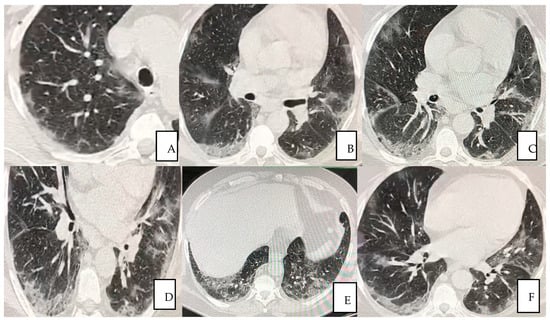

The first pulmonary high-resolution computed tomography (HRCT) scan at the admission on November the 18th revealed extensive bilateral damages as shown in Figure 1A–F. The CT scan results at the time of the admission often confirmed severe deteriorated lung structures and functionality.

Figure 1.

(A–F) A 56-year-old man presented with fever for 3 days, accompanied by anuria, asthenia, general malaise and positive to COVID-19 (A–E) Pulmonary HRCT obtained on 18 November 2020 showed multiple peripheral patchy ground glass opacities bilaterally being the lower lobes the most involved areas in (F).